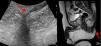

The first case was a 73-year-old man who was referred to our department from general surgery owing to suspected HS. He presented an indurate nodule on the left side of the perineum that was painful on palpation and had appeared a year earlier (Fig. 1A). The patient presented no other skin lesions in the area or in other skin folds and reported no gastrointestinal discomfort. An ultrasound examination was performed using a high-resolution probe (Esaote Mylab Class C, 18MHz), which showed a broad hypoechoic band connecting the skin lesion with the anal canal, with no associated abscesses. Color Doppler mode revealed no vascularization (Fig. 1B). These findings suggested a diagnosis of primary perianal fistula and we requested a perianal transcutaneous ultrasound examination (Fig. 2) and a magnetic resonance imaging study (Fig. 2b); the patient was referred to general surgery for surgical treatment.

Clinical and ultrasound images of the first patient. A,Violaceous nodules with an erosive central region on the left buttock. B,Hypoechoic subcutaneous band corresponding to the fistular path, which connects the visible lesion with the perianal skin. Thickening of the dermis and dilated follicles can also be seen (red arrow).